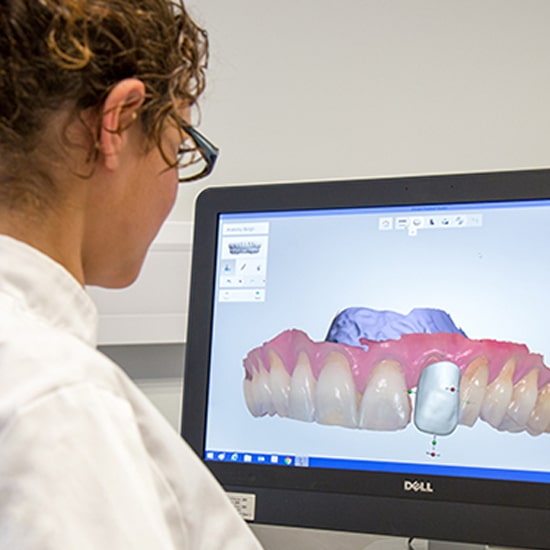

Scanning

01

Designing and

planning of

implants

02

Complete oral evaluation with digital imaging.

Personalized plan for your smile goals.

Minimally invasive, comfort-focused techniques.